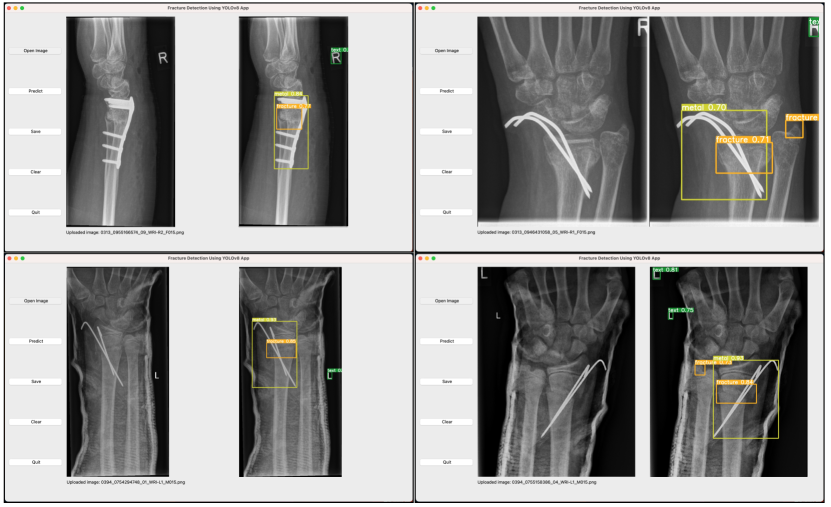

After completing model training, we utilize a Python library that includes the Qt toolkit, PySide6, to develop a Graphical User Interface (GUI) application. Specifically, PySide6 is the Qt6-based version of the PySide GUI library from the Qt Company.

According to the model performance evaluation results in Table 5 and Table 6, we choose our model with YOLOv8s algorithm and the input image size of 1024, to perform fracture detection. Our model is exported to onnx format, and is applied to the GUI application. Figure 7 depicts the flowchart of the GUI application operation on macOS. As can be seen from the illustration, our application is named “Fracture Detection Using YOLOv8 App”. Users can open and predict the images, and save the predictions in this application. In summary, our application is designed to assist pediatric surgeons in analyzing fractures on pediatric wrist trauma X-ray images.

Furthermore, we develop an application named "Fracture Detection Using YOLOv8 App" to analyze pediatric wrist trauma X-ray images for fracture detection. Our application aims to assist pediatric surgeons in interpreting X-ray images, reduce the probability of misclassification, and provide a better information base for surgery. The application is currently available for macOS, and in the future, we plan to deploy different sizes of our model in the application, and extend the application to iOS and Android. This will enable inexperienced pediatric surgeons in hospitals located in underdeveloped areas to use their mobile devices to analyze pediatric wrist X-ray images.